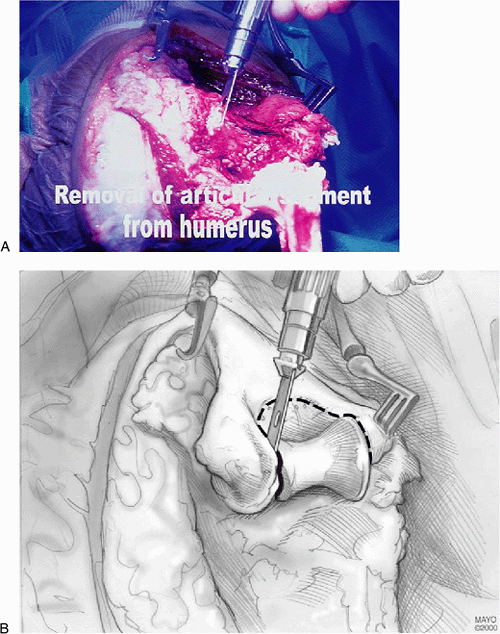

the patient’s head, the humerus is prepared for insertion of the

humeral component. First, part of the articular surface of the trochlea

is removed, together with the trochlear notch, and a small reamer is

passed up the intramedullary canal (Fig. 17-8).

![]() |

|

Figure 17-8. A,B:

The trochlear portion of the distal humerus is removed with an oscillating saw and the medullary canal of the humerus is identified. |